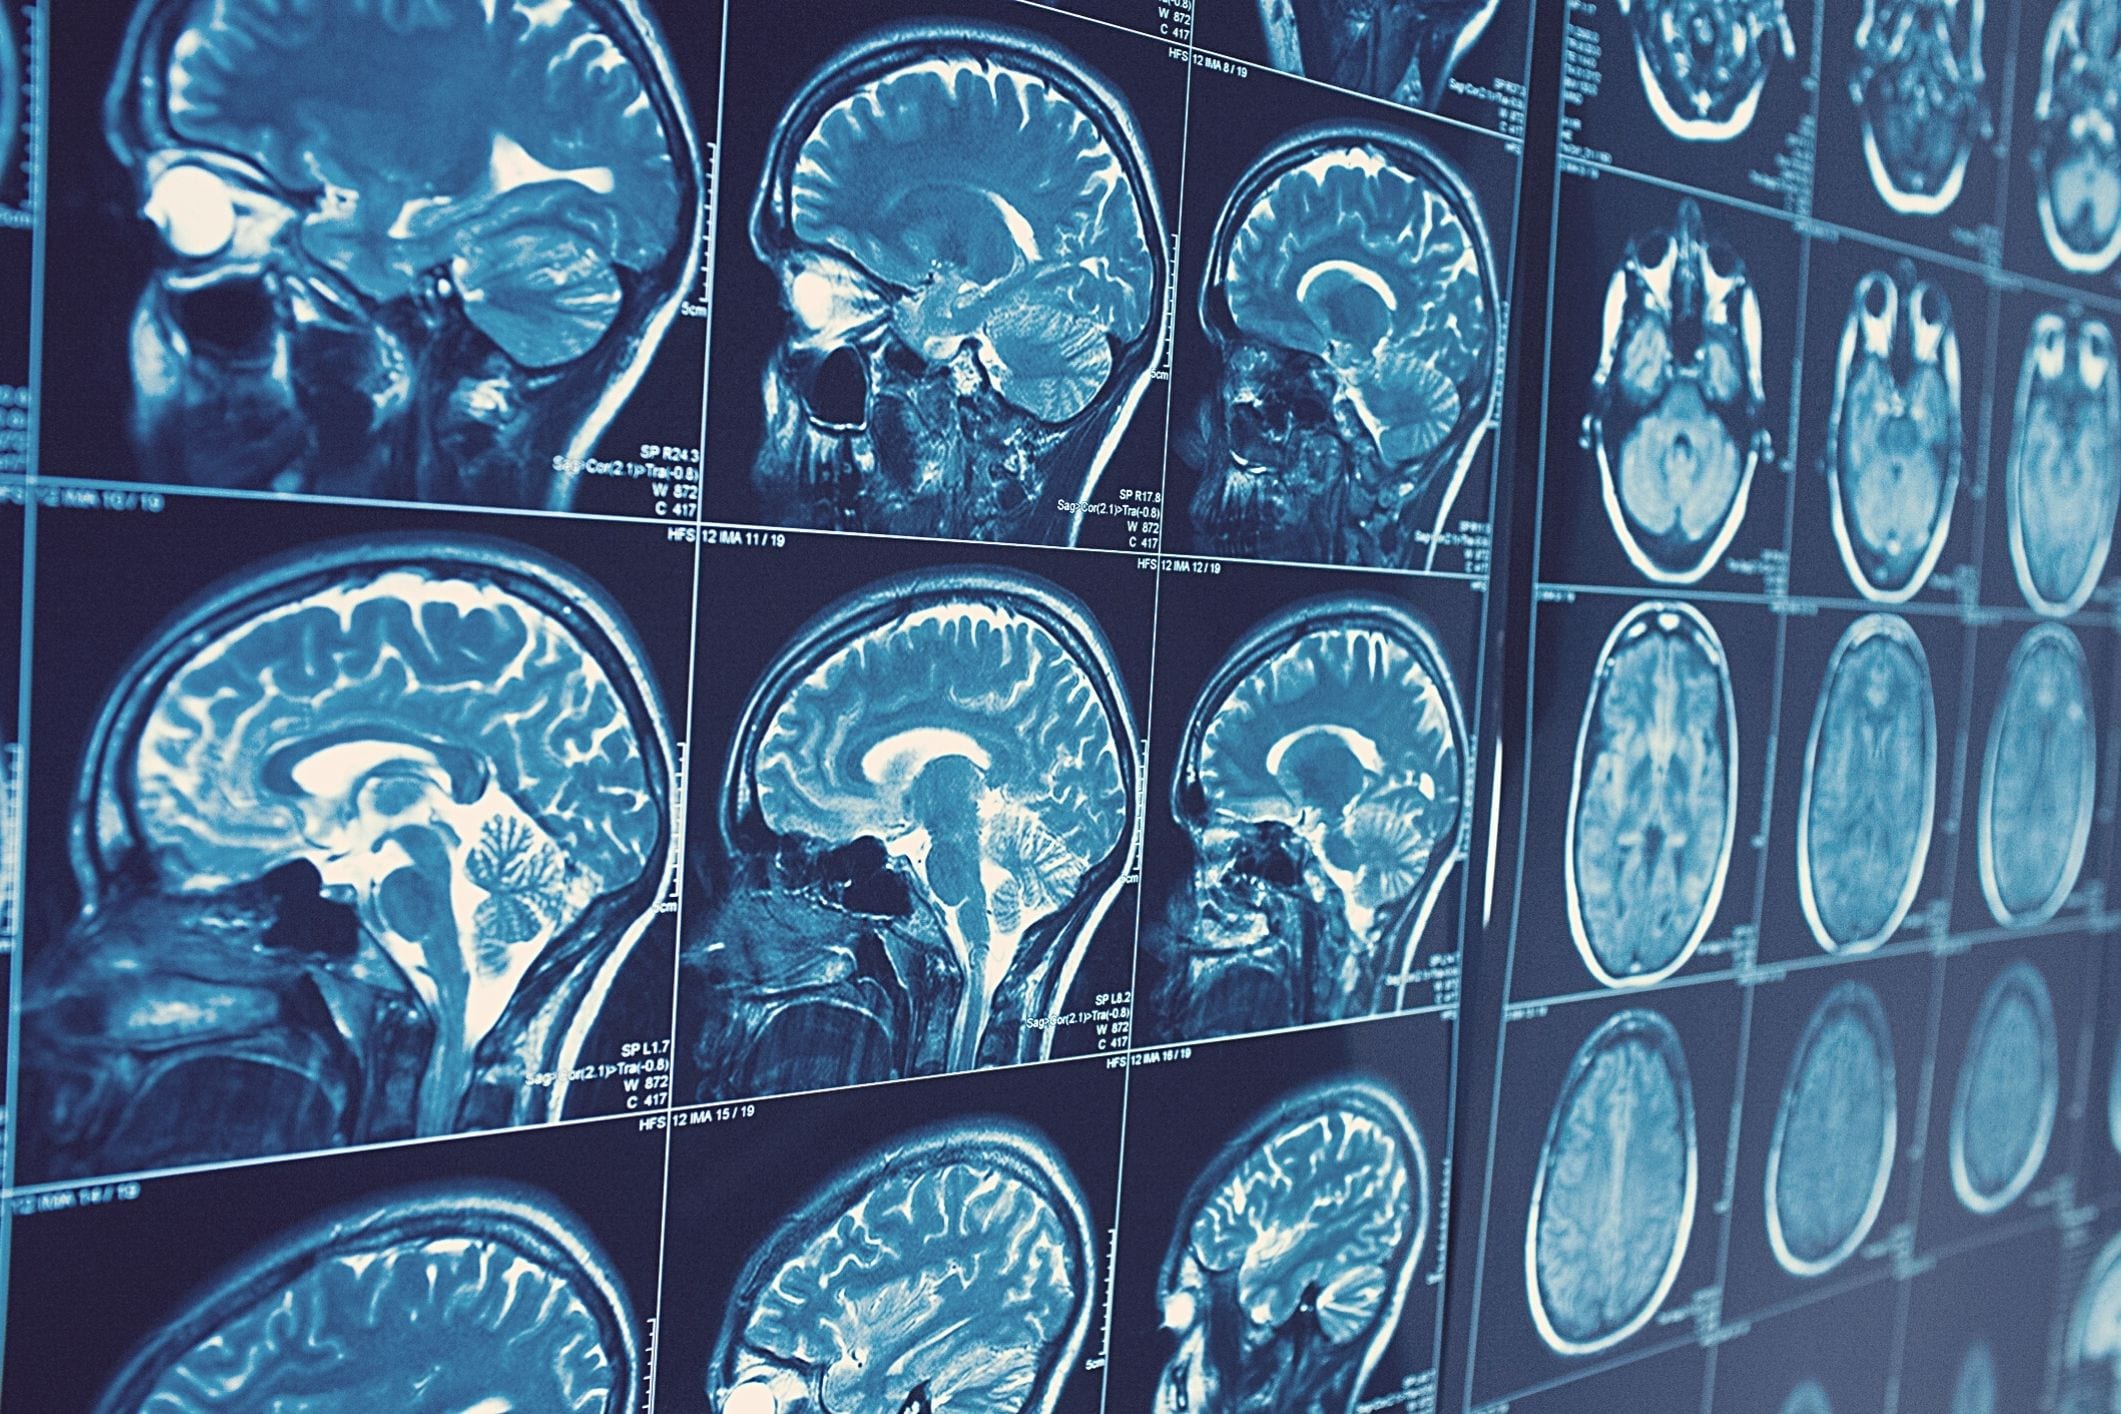

Alzheimers brain scan

Published in the Journal of Alzheimer’s Disease Reports, the research shows that aluminium is co-located with phosphorylated tau protein, producing tangles within brain neurons of early-onset or familial Alzheimer’s disease.